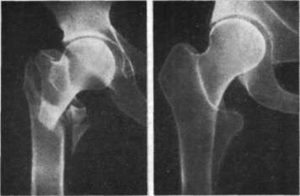

Рис.4. а. межвертельный перелом бедра; б. интрамедуллярный остеосинтез перелома бедренной кости штифтом.

Рис.5. а. чрез- подвертельный оскольчатый перелом проксимального отдела бедра; б. интрамедуллярный остеосинтез перелома бедренной кости штифтом с блокированием.